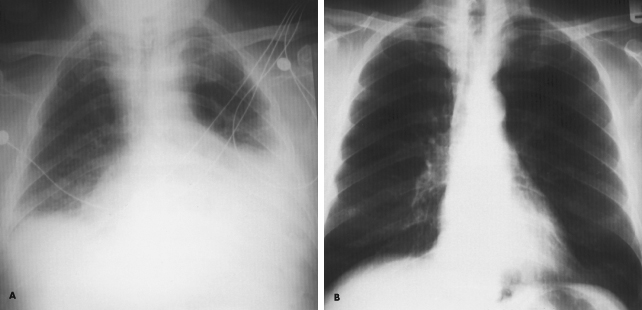

Over the previous 6 months, a 59-year-old man had experienced lethargy, fatigue, poor appetite, cold intolerance, and abdominal distention. His vital signs were normal; physical examination revealed periorbital and pretibial edema, distant heart sounds, and delayed reflexes.

An ECG showed low voltages, and a chest film revealed generalized enlargement of the cardiac silhouette with a globular configuration and small, bilateral pleural effusions (A). An echocardiogram confirmed the presence of a large pericardial effusion. Subsequent laboratory studies revealed serum thyroid-stimulating hormone levels of 50 µU/mL, serum thyroxine levels of 4.5 µg/dL, and a reverse triiodothyronine uptake of 24.7 ng/dL. These findings are consistent with primary hypothyroidism. Thyroid replacement therapy was initiated. One year later, the chest film changes had resolved (B).

The recognition of pericardial effusions is important because these may, in a short time, lead to cardiac tamponade. Causes of such effusions include trauma, pericarditis, renal failure, Dressler’s syndrome, neoplastic disease, and immunologic disease (particularly rheumatoid arthritis and systemic lupus erythematosus). Pericardial effusion is a common finding in myxedema, occurring in up to one third of all cases.

(Case and films courtesy of Drs Eugene Wong and Peter Petropoulos.)